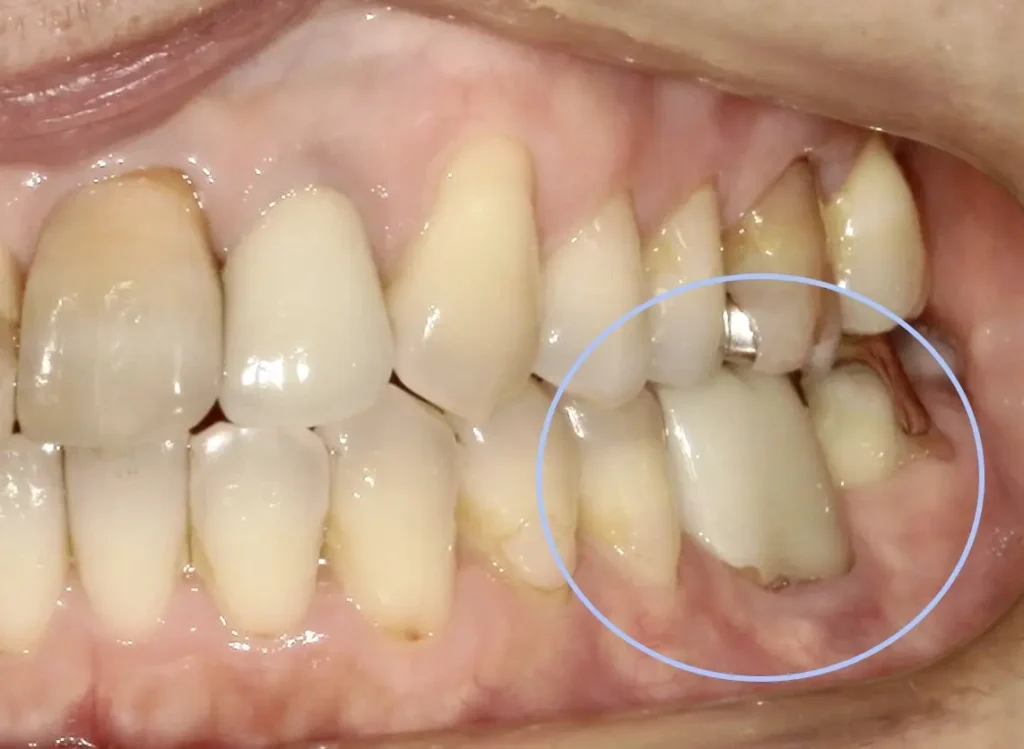

治療前

左下の奥歯が根が割れて保存不可能です。奥の咬合わせの余っている親知らずを移すことににしました。移植した歯は、根管治療とクラウン修復が必要です。

奥3番目の歯の根が割れています。

3年経過口腔内写真

お手入れもうまくいって炎症もありません。

奥から2番目、審美性も機能も維持されています。